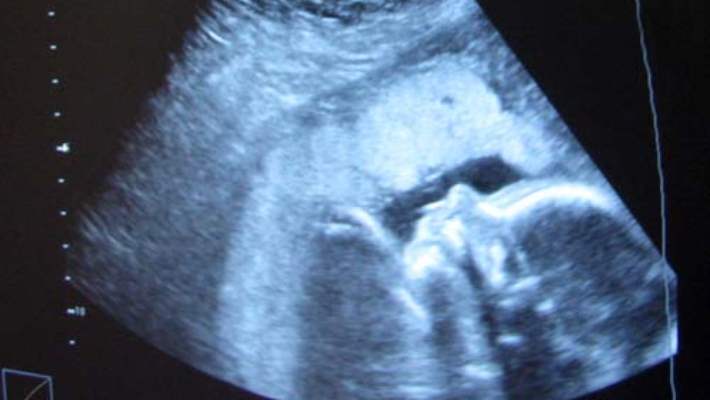

Hamileliğin 12. Haftasında Bebek Hakkında Neler Bilinebilir?